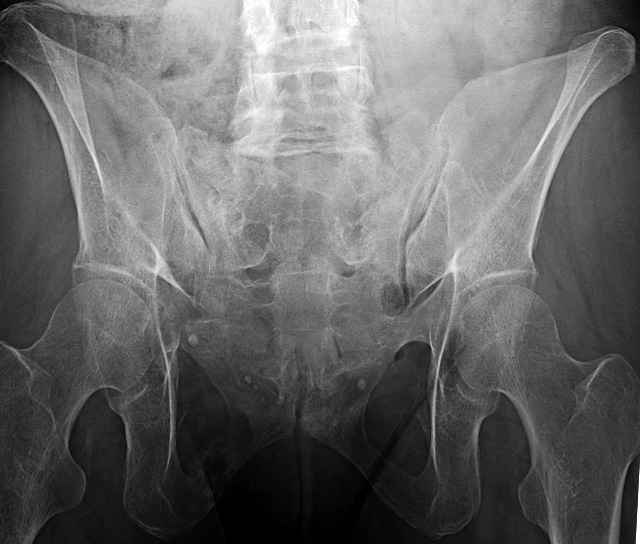

54 yo Female Fell c/o Pain

Initial Films

?Instability on Exam - Limited by Pain

NonOp Initial Mgmt

3 Months After Fall

Continued Pain & Immobility

(+) Instability to Compressive Manual Exam